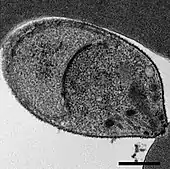

A Plasmodium knowlesi merozoite attaching to a red blood cell